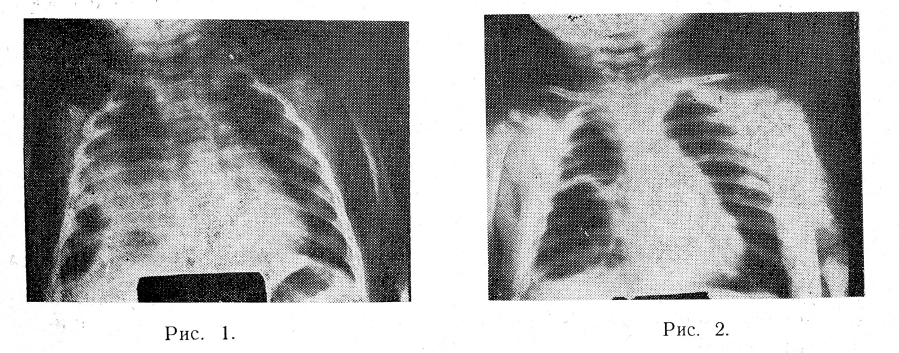

Нами исследованы 16 детей с пневмониями на фоне расстройств питания, у 4 из них была острая диспепсия. Возраст больных — от 3 до 9 месяцев. У детей с гипотрофией пневмонии чаще были сливными, имели вялое, затяжное течение; у 2 из них образовались дисковидные ателектазы и эмфизематозные буллы. Так, больная А., 3 мес., поступила в клинику с правосторонней сливной стафилококковой плевропневмонией на фоне слабо выраженной гипотрофии. На рентгенограмме от 28/II почти на всем протяжении правого легкого определяется довольно интенсивное затенение с отчетливой полостью в нижне-наружных отделах (рис. 1). Поскольку состояние ребенка по сравнению с предыдущими днями стало лучше, было высказано предположение, что полость представляет собой не осложненную эмфизематозную буллу — важный патогномонический признак стафилококковой пневмонии. Состояние больной с каждым днем становилось лучше. На рентгенограмме от 16/III (рис. 2) при продолжающемся лечении эмфизематозная булла значительно увеличилась, стала «напряжённой»,

над ней появилась еще одна небольшая воздушная полость. Тень инфильтрации в легких намного уменьшилась, отмечается тонкий слой выпота в плевральной полости. На рентгенограмме от 23/ІII обе полости отчетливо видны, но уменьшились в размерах. К этому времени никаких других клинических данных о каком-либо процессе в легких не осталось. Ребенок бодрый, активный; температура, картина крови нормализовались. Полное исчезновение воздушных булл наступило только через 1,5 мес. после первоначального выявления.